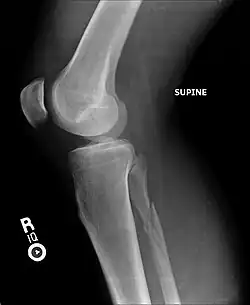

Ankle radiographs are used to detect widening of the tibiofibular syndesmosis or medial clear space. The medial clear space is the area between the talus of the ankle and the medial malleolus. Damage to the deltoid ligament and syndesmotic ligaments result in mortise instability, causing the talus to laterally shift and widen the medial clear space.[4][12] A clinical study, conducted in 2006 and published in the Journal of Bone and Joint Surgery, found that the medial clear space size of a normal ankle and an injured ankle measured at 4 millimetres and 5.4 millimetres in length respectively.[11] To confirm diagnosis, full-leg radiographs are used to inspect for fractures of the proximal fibula and widening of the interosseous clear space (or tibiofibular clear space). The interosseous clear space is the area between the medial side of the fibula and lateral side of the tibia. A peer-reviewed study, published in Injury in 2004, found that an interosseous clear space greater than 10 millimetres indicates diastasis of the syndesmotic ligaments.[4]

If necessary, Computed Tomography (CT) or Magnetic Resonance Imaging (MRI) may also be used to clarify diagnosis. MRI scans can check for interosseous membrane or tibial tubercle damage if high instability of the ankle is diagnosed.[8][11] Arthroscopy may be used to diagnose a syndesmotic lesion but is often not recommended due to operative difficulty.[13] Stress radiographs of the ankle are used to assess the integrity of the deltoid ligament and tibiofibular syndesmosis.[9][13] The size of the medial clear space can also be measured using stress radiography.[11]

X-ray, CT, or MRI scans can be used to diagnose the extent of the Maisonneuve fracture's damage and determine whether it is a simple or comminution fracture.[8] During diagnosis, a supination-external rotation pattern of injury may also be concluded if there is an isolated fracture of the posterior tubercle of the tibia.[9]